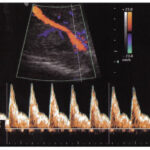

Ofrecemos servicios de ecografía obstétrica avanzada (genética, estructural, Doppler) y seguimiento experto de embarazos de alto riesgo, utilizando tecnología de punta para diagnósticos precisos

Servicios alineados con las directrices de la Fetal Medicine Foundation (FMF) y la International Society of Ultrasound in Obstetrics and Gynecology (ISUOG).